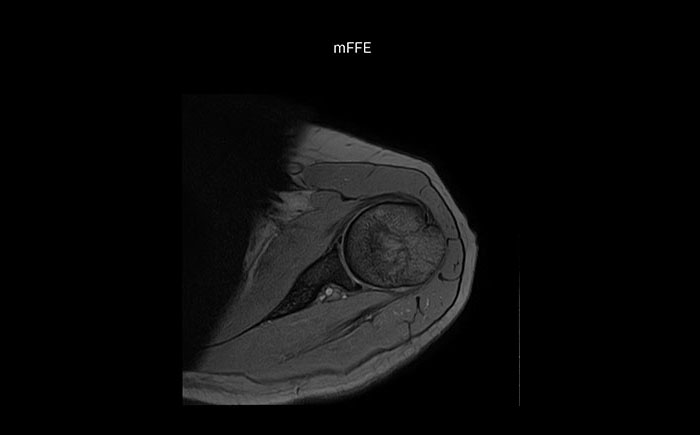

Shoulder MRI with high quality, large coverage

The Prodiva shoulder coil is very flexible and has large coverage, which makes good positioning easier, and that contributes to the superb image quality and high SNR that we get in our shoulder exams.

Shoulder MRI with high quality, mFFE

Scan time 4:19 min, FOV 160 mm,

acq voxels 0.55 x 0.80 x 3.0 mm.